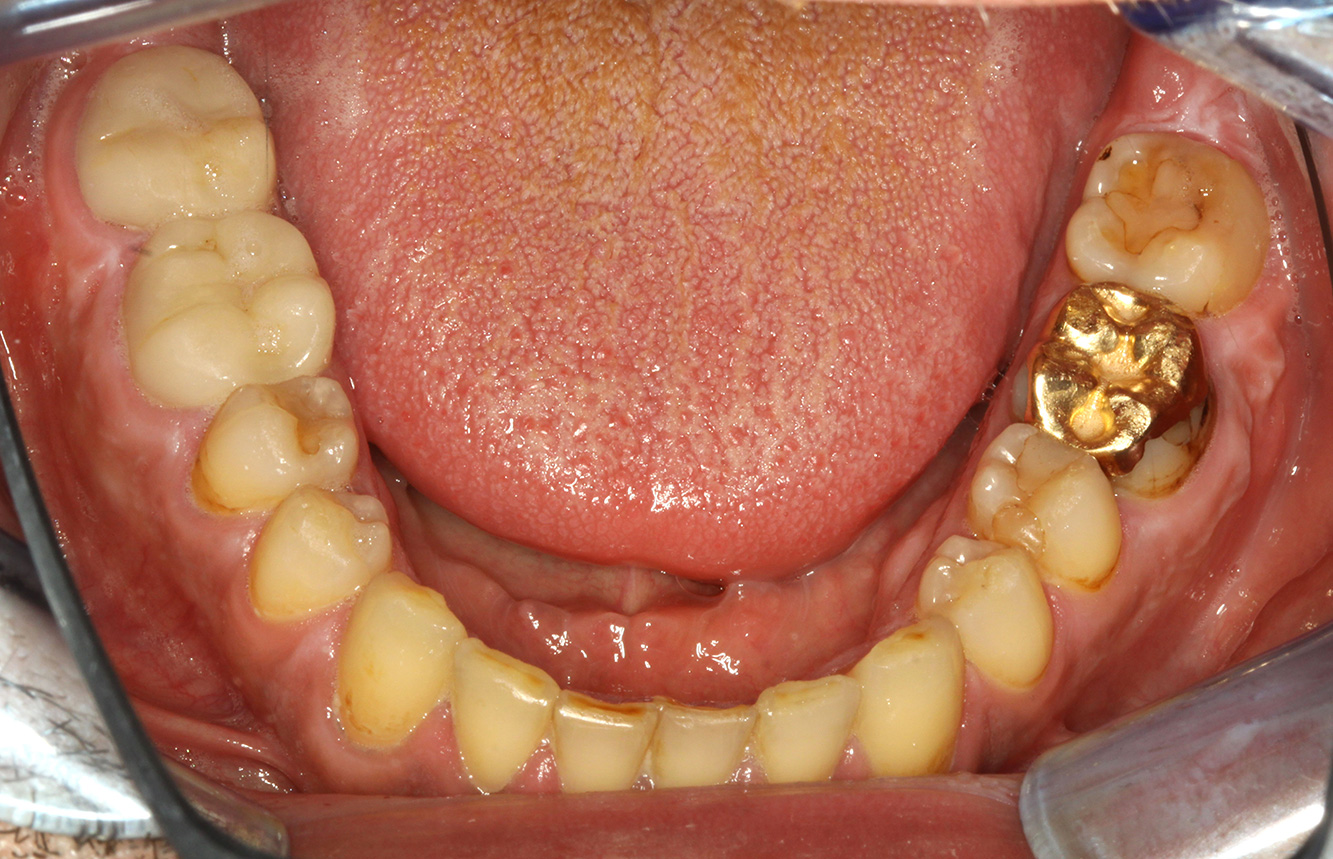

Il paziente ha 39 anni e in passato è stato sottoposto ad un intervento per la sostituzione della valvola aortica dovuta a insufficienza valvolare ed endocardite. Assume regolarmente l'ASS 100 come anticoagulante. Per quel che riguarda lo stile di vita, il regime alimentare seguito dal paziente è classificato come “dieta che favorisce la formazione della carie”, per via del consumo regolare di cibi ad alto contenuto di zuccheri e dei sei-sette pasti consumati al giorno. La salute orale del paziente indica un rischio moderato di carie, con lesioni attive. Il rischio di parodontite è basso, tuttavia il paziente è affetto da gengivite. Si formulano quindi i seguenti consigli per il trattamento di profilassi.